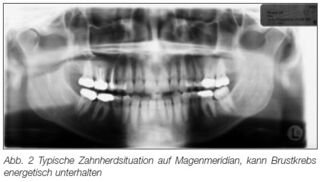

Bild aus einem Artikel von Thomas Rau bei "Sanum-Post" mit Bezug zur Meridian-Lehre aus der TCM[1]